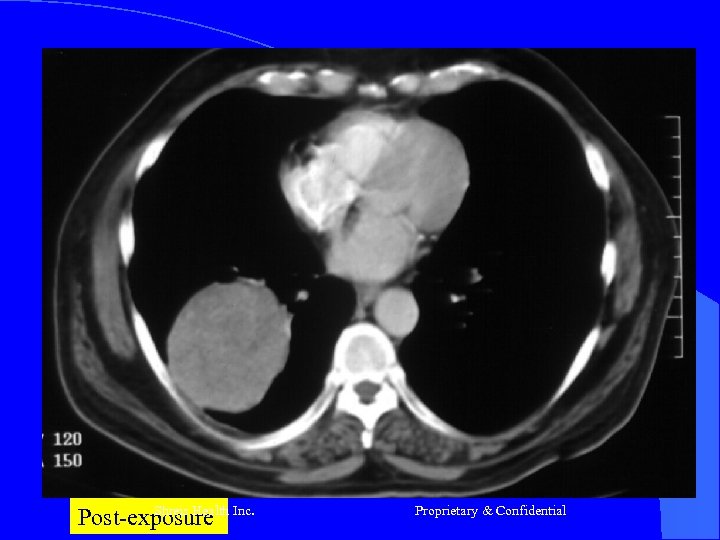

Case- 1 l l l Mr R, 68 yrs Nov-2003 -Ca Lung RLL T 2 N 0 (Adeno ca) Chemo – (Carbo + Eto) 3 # till March 2004 April 2004 – Prog of disease (vide CT) Presented – Cough Hemoptysis - Breathlessness - Pallor - Debility Shreis Health Inc. Proprietary & Confidential

Case 1 RFQMR-1#26/11/2004 – 09/12/2004 2# 24/12/2004 – 07/1/2005 l CT – Jan 2005 – Aug 2005 - Static l Now No Complaints - Energetic - Walks 30 m daily Appetite Good l Shreis Health Inc. Proprietary & Confidential

Shreis Health Inc. Pre-exposure Proprietary & Confidential

Shreis Health Post-exposure Inc. Proprietary & Confidential

Post-exposure Inc. Shreis Health Proprietary & Confidential